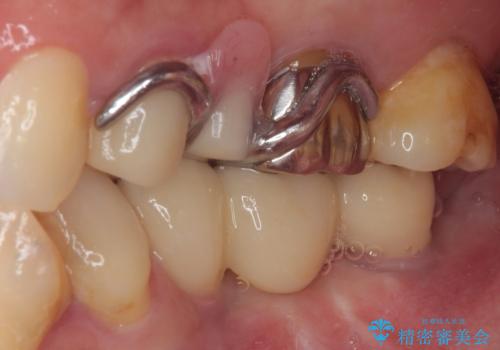

左下小臼歯は根管治療で対応する予定でしたが、診断のために歯肉を開いたところ頬側に垂直破折が認められたため、抜歯即時埋入インプラントによる補綴治療を選択することとしました。

右下は大臼歯部の歯は抜歯即時埋入インプラントにて、手前の歯は保存して補綴治療を行うこととしました。

インプラント埋入時に十分な安定値を得ることができたため、速やかに仮歯を装着し、最小限の通院回数で治療を終えることができました。